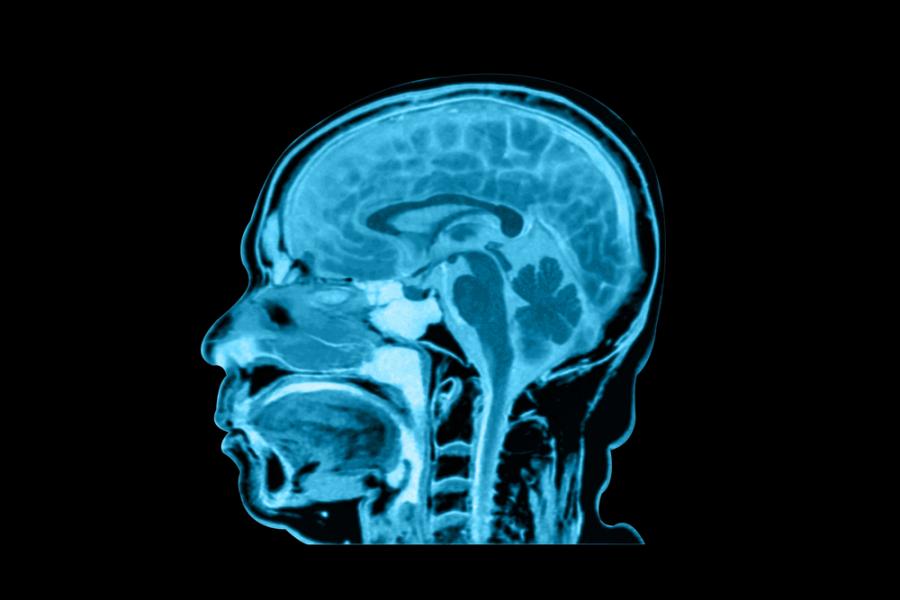

Наскоро д-р Марк Абът, докторант от Държавния медицински университет в Охайо, разказа в Twitter за среща със студент, изненадан от големината на човешкия език. По-конкретно – как изглежда при сагитално сечение (т.е. в случаите, когато тялото се разделя на лява и дясна секция) – това е възможно както чрез сканиране, така и при специална техника на дисекция.

За да разгледаме човешката глава по този начин например (особено ако пациентът е жив), можем да прибегнем до помощта на магнитно-резонансната томография (ЯМР). Чрез нея могат да бъдат създадени и някои наистина невероятни видео клипове, както и сами ще се убедите съвсем малко.

Видеото показва как човек бийтбоксва, докато се намира в ЯМР – по този начин можете да видите как езикът се изкривява от една много по-различна перспектива. Невероятно е, нали?